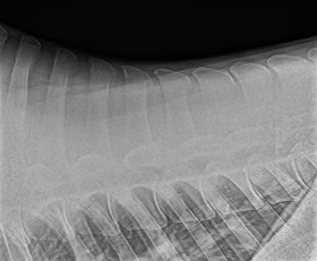

Vortrag „Kissing Spines“ von Dr. Nils Adolphsen

Bei der Fortbildungsveranstaltung in unserer Klinik mit derbymed-Livisto im November 2019 hat Dr. Nils Adolphsen zum Thema „Kissing Spines – Wo stehen wir heute unter besonderer Berücksichtigung der OP-Techniken“ einen informativen Vortrag gehalten.

Wie immer gerne zum Nachlesen für alle Interessierte: Vortrag